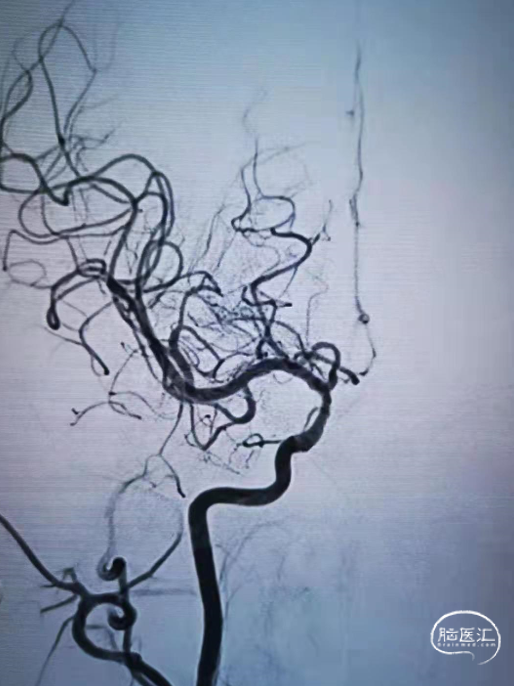

半年后复查造影支架内再狭窄。

2

加奇SacSpeed®2.0×15mm球囊预扩张后2×10mm药涂球囊扩张。

3

狭窄明显改善。

对于支架内再狭窄患者,药物球囊扩张治疗可抑制内膜增生,降低再狭窄率